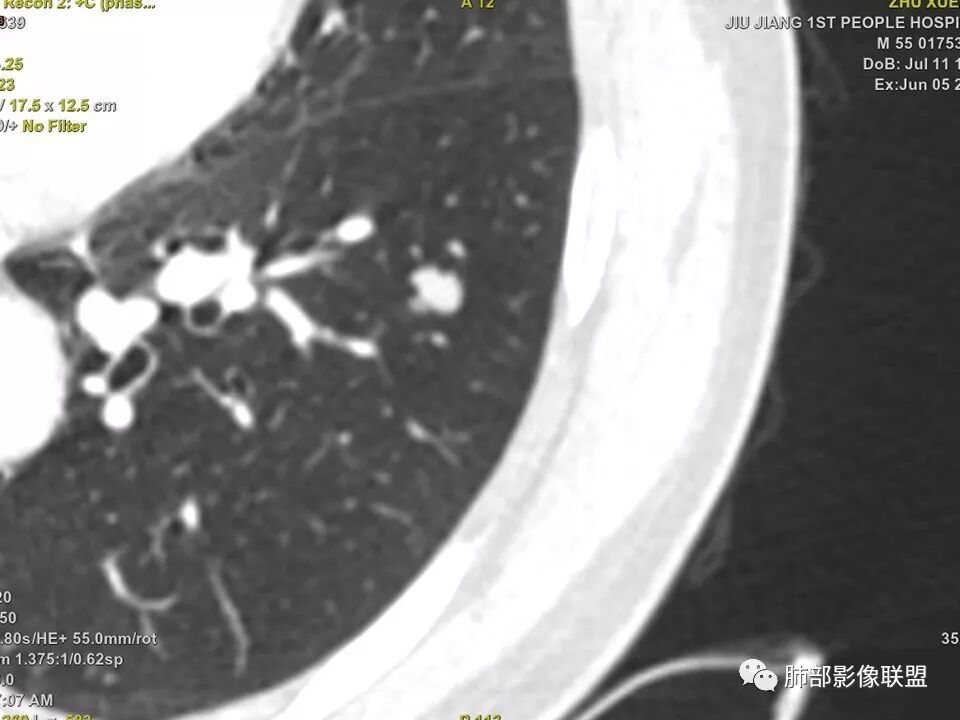

病灶多结节融合,有分叶,也支气管截断,有细小血管连接,考虑恶性结节,周围型肺癌。

支气管截断,边缘有收缩膨隆,分叶但毛刺不明显,无强化,小病灶内坏死,周围有卫星灶,考虑炎性肉芽肿,鉴别癌

左下肺前内基底段结节灶,边缘分叶,相应支气管截断,增强后轻度强化,中央可见坏死。考虑麟癌。

左肺下叶结节,边缘分叶,支气管阻塞,轻度强化,考虑恶性肿瘤

肺软骨瘤好发年龄40~50 岁,男女发病无明显差异。多位于两肺外带,右肺多见。无明显临床症状,常在体检时偶然发现。若病灶发生于大支气管壁或病灶较大压迫支气管时(少见)可引起刺激性咳嗽、咳痰等症状。